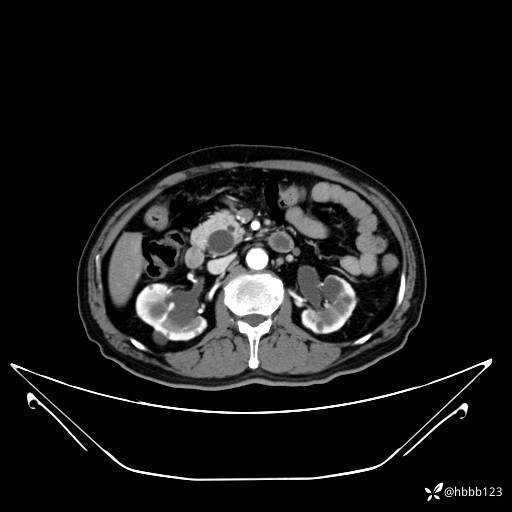

动脉期: